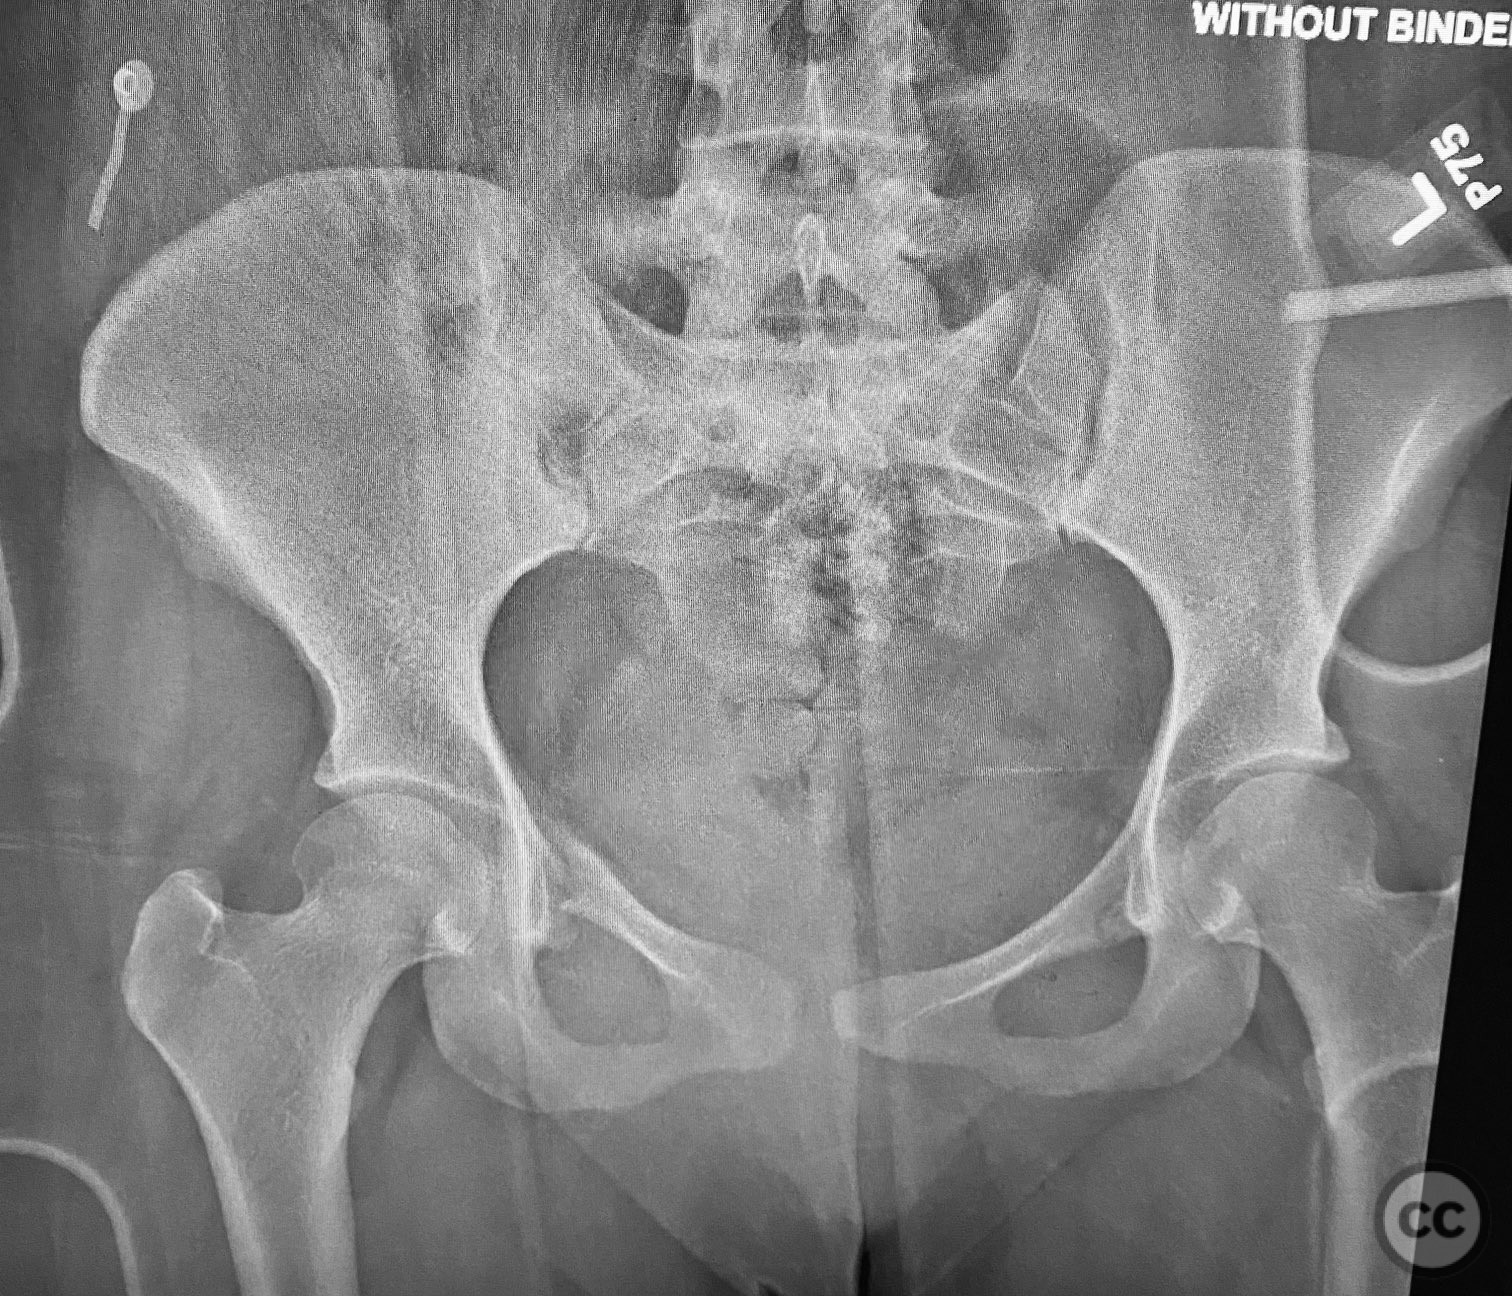

Clinical and radiological findings:  A young adult female sustained a high-energy pelvic injury following a motorcycle crash. She was hemodynamically stable on presentation, with normal neurovascular examination and no evidence of genitourinary, vaginal, or rectal injury. She reported pain localized to both anterior and posterior pelvic regions. Initial plain radiographs (with and without pelvic binder) demonstrated multiple anterior ring fractures and dislocations. The binder images obscured the full extent of injury. Further intraoperative fluoroscopic imaging (AP, inlet, and with lower extremities in "lotus" position) revealed bilateral sacroiliac (SI) joint disruptions (right greater than left), bilateral superior/inferior pubic ramus fractures (right greater than left), and symphyseal diastasis. Notably, the right pubic ramus demonstrated excessive curvature, complicating potential percutaneous screw fixation. AO/OTA classification: 61-C1.3 (bilateral complete disruption of the posterior arch with associated anterior ring injury). Young-Burgess classification: APC III.

Planning remarks:  The preoperative plan included open reduction and internal fixation (ORIF) of the displaced right pubic ramus fracture and symphyseal diastasis via an anterior approach, with acceptance of indirect closed reduction of the SI joints. Percutaneous trans-sacral screw fixation was planned for stabilization of the posterior pelvic ring. Due to the complex curvature of the right ramus, straight screw fixation was deemed unsuitable.